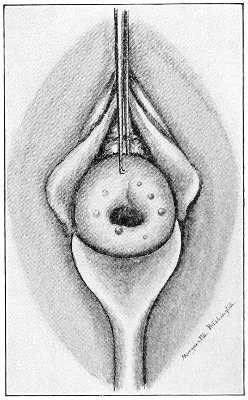

Fig. 18.—Cyst of the right vulvo-vaginal gland (Hirst).

Cysts of the gland may be unilocular if formed at the expense of a single lobule of the gland, or multilocular if several lobules enter into their formation. These cysts may attain the size of the fetal head (Fig. 18).

These cysts contain clear yellow or chocolate-colored 42 fluid. The diagnosis of cyst of the vulvo-vaginal gland is usually not difficult. If we are in doubt in regard to the fluid character of the tumor, this may be determined with the exploring-needle.

Inguinal hernia, hydrocele of the canal of Nuck, cysts of the round ligament, and sacculated cysts of old hernial sacs may be mistaken for cysts of the vulvo-vaginal glands. In such cases, however, the tumor lies more in the upper and outer part of the labium majus, and extends to, and may be connected with, the external inguinal ring.

Cysts of the vulvo-vaginal glands should be treated by free incision and packing, or by extirpation. If the sac is emptied by the aspirator or by a small incision, it will refill. The best method is to extirpate the cyst. In case there has been no inflammatory action binding the cyst to surrounding structures, extirpation without rupture is easy. If rupture occurs, the cyst-wall may be dissected off with the knife or removed with the curved scissors. The wound may be immediately closed with deep and superficial sutures.